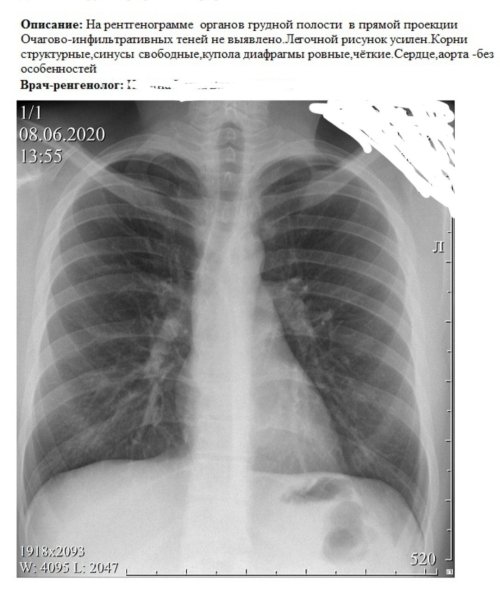

Усиление сосудистого рисунка легких на рентгене - это явление, которое может быть наблюдаемо при проведении рентгенологического исследования органов дыхания. В результате усиления сосудистого рисунка, на снимке становятся более заметными сосуды, расположенные внутри легких. Это может свидетельствовать о различных патологических процессах, таких как воспаление легких, обструкция дыхательных путей или сердечная недостаточность. Усиление сосудистого рисунка является важным признаком для постановки диагноза и выбора оптимального лечения. Однако, для точной интерпретации рентгеновского снимка необходимо учитывать и другие клинические данные, а также провести дополнительные исследования, если необходимо.